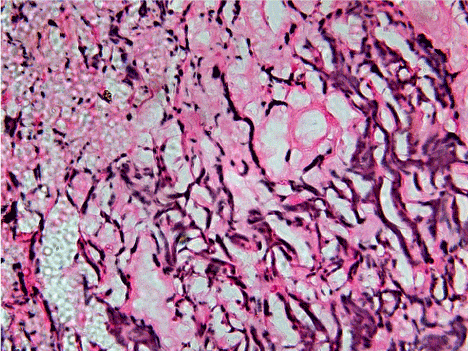

Figure 1. 40X view of moderately differentiated squamous cell carcinoma showing relatively short, thin but dense and fragmented, scattered reticulin fibers of varying degree from dark to light intensity of staining and haphazardly arranged throughout connective tissue stroma.